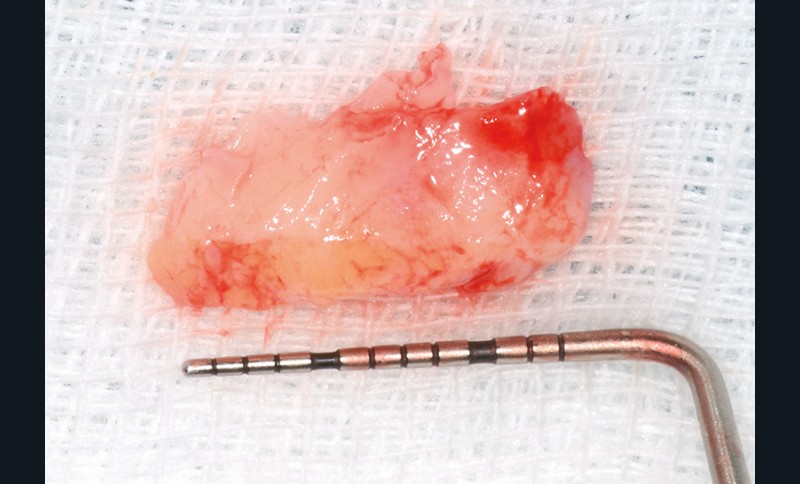

bibli/2.3.21.jpgPrélèvement du conjonctif le plus fin possible.

Évaluation préopératoire de la muqueuse palatine, choix des zones de prélèvement.

bibli/2.2.jpgPrélèvement des greffons conjonctifs.

bibli/2.2.jpgPrélèvement des greffons conjonctifs.

Les sites donneurs se trouveront en avant de la première molaire.